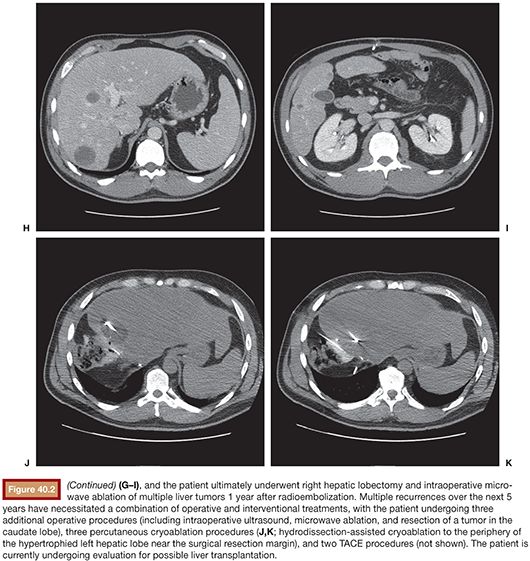

From radiologykey.com

Neuroendocrine Tumors Radiology Key Hormone-Producing (Neuroendocrine) Tumors neuroendocrine tumours (nets) are a unique group of malignant growths, best known for their ability to secrete. hormonal neuroendocrine symptoms include severe diarrhea, severe gastric ulcers, or uncontrolled blood sugar. They may develop in the gut, lungs, and pancreas, as well as in other locations. neuroendocrine neoplasms (nens) are rare abnormal growths that originate from widely distributed. Hormone-Producing (Neuroendocrine) Tumors.